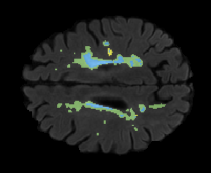

We evaluated our method in segmenting WMH from T1-w images using: a) Synthesized FLAIR images by treating the synthesis as a preprocessing step – we will refer to this method as offline synthesis; b) Synthesized FLAIR images using the proposed method, and c) without any synthesis – we will refer to this method as Unimodal. Baseline methods are illustrated in Figure 2

Table 2: Segmentation results for all proposed methods, each column represent a different slide in the image, blue areas are regions which were correctly labeled, false positives are shown in green, and false negatives in yellow

In order to better understand the above results, we visually analyzed the output segmentation performed for each method. Table 2 shows the results for three different slices (one slice per column). As illustrated, the proposed method is able to produce less false positives. It is also important to note that, unimodal segmentation is the one that produces more false positives, showing the advantage of using synthetic data. Regarding the nature of false positives, it can be easy to see in the third column a large number of false positives are on the border of periventricular lesions for the Unimodal method in comparison to the proposed method. Also from the first and second column, it can be observed that Unimodal tend to produce more small regions of false positives near to cortical areas. Removing such false positives requires additional post-processing steps, therefore, it is of value avoid this kind of over-segmentation. It can also be noted that synthesis methods tend to produce the same kind of false negatives, this may be due to the blurring effects in synthesized images since the information available during testing is limited – which otherwise is available from a FLAIR sequence.